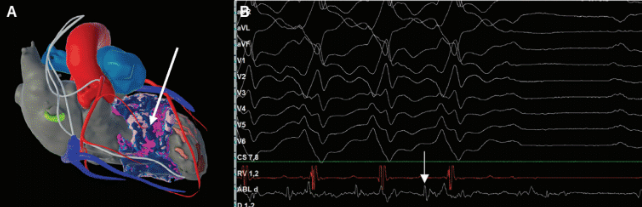

Another example of VT ablation in a patient with hypertrophic cardiomyopathy is shown in Figure 4. Deep septal scar is demonstrated by late iodine enhancement on cardiac CT processed with inHEART. Ablation in this area terminated the patient’s clinical VT.